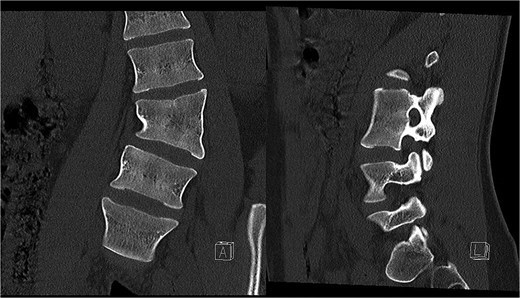

Preoperative CT demonstrating L3 hemivertebra; anteroposterior view (A) on the left side of the image, and lateral view (L) on the right side of the image.

A 24-year-old female with congenital scoliosis caused by a semi-segmented hemivertebra at L3 (Figs 4 and 5) was under follow-up at our institution for chronic back pain and left leg pain, without motor deficits. She had been referred to our institution three years earlier, at which time surgical resection was indicated. However, the procedure was postponed due to patient's personal reasons.

CT-based 3D reconstruction revealed a semi-segmented hemivertebra at L3, resulting in a 32° Cobb angle of congenital scoliosis (Fig. 4). We decided to perform hemivertebra resection, L3 laminectomy, L2-L4 fixation with L3–4 cage fusion, and scoliosis correction. CT-based resection was 3D planned using EBS software (Fig. 6). Fixation from L2 to L4 was achieved using pedicle screws under fluoroscopic guidance, followed by L3 laminectomy. After accessing the L3–L4 disc space, a 3D real-time EMN-guided total resection of the L3 hemivertebra was performed (Fig. 6), and a cage with autogenous bone graft was inserted at the L3–L4 level. The left-sided L3 nerve was found to have an accessory branch, which was successfully preserved. Scoliosis was corrected using standard deformity correction maneuvers.